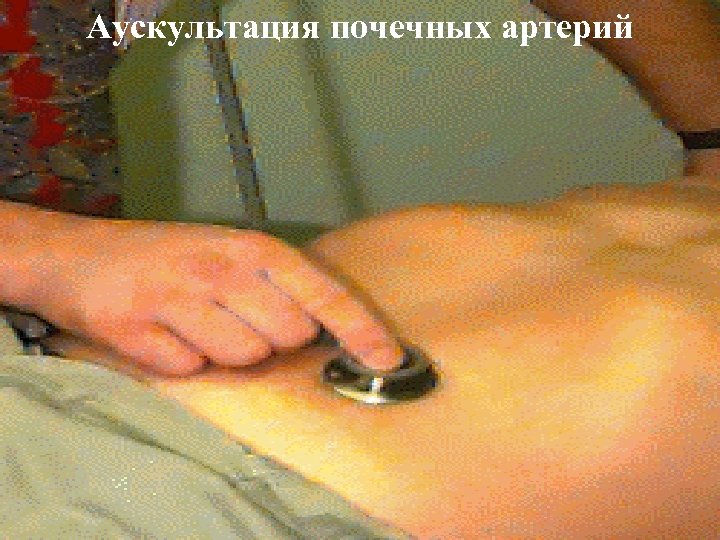

Физические методы исследования § Осмотр (отеки, цвет кожи, геморрагии, с-м «бабочки» , сетчатое ливедо, следы расчесов, стигмы дисэмбриогенеза) § Пальпация -почек (опухоль, нефроптоз, киста, поликистоз) -наполненного мочевого пузыря § Перкуссия -с-м поколачивание, с-м Пастернацкого ( «+» при пиелонефрите, паранефрите) -наполненный мочевой пузырь § Аускультация (систолический шум при стенозе почечных артерий)

Аускультация почечных артерий